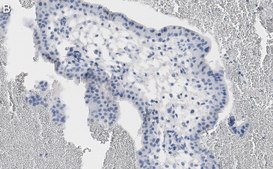

Immunohistochemistry (Paraffin) Analysis: A 1:100 dilution from a representative lot detected NF-kB p65 subunit in human placenta tissue sections.